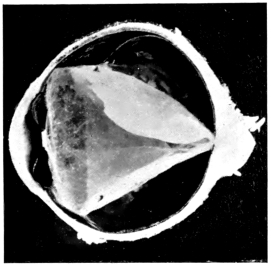

PLATE IV.

22.

LENS DISLOCATED BEHIND RETINA

curly bracket span

23.

FISTULA OF THE CORNEA

24.

CAPSULO-CORNEAL SYNECHIA

25.

RETINO-CORNEAL SYNECHIA

26.

SCLERAL FISTULA

27.

"    " (MAGNIFIED)